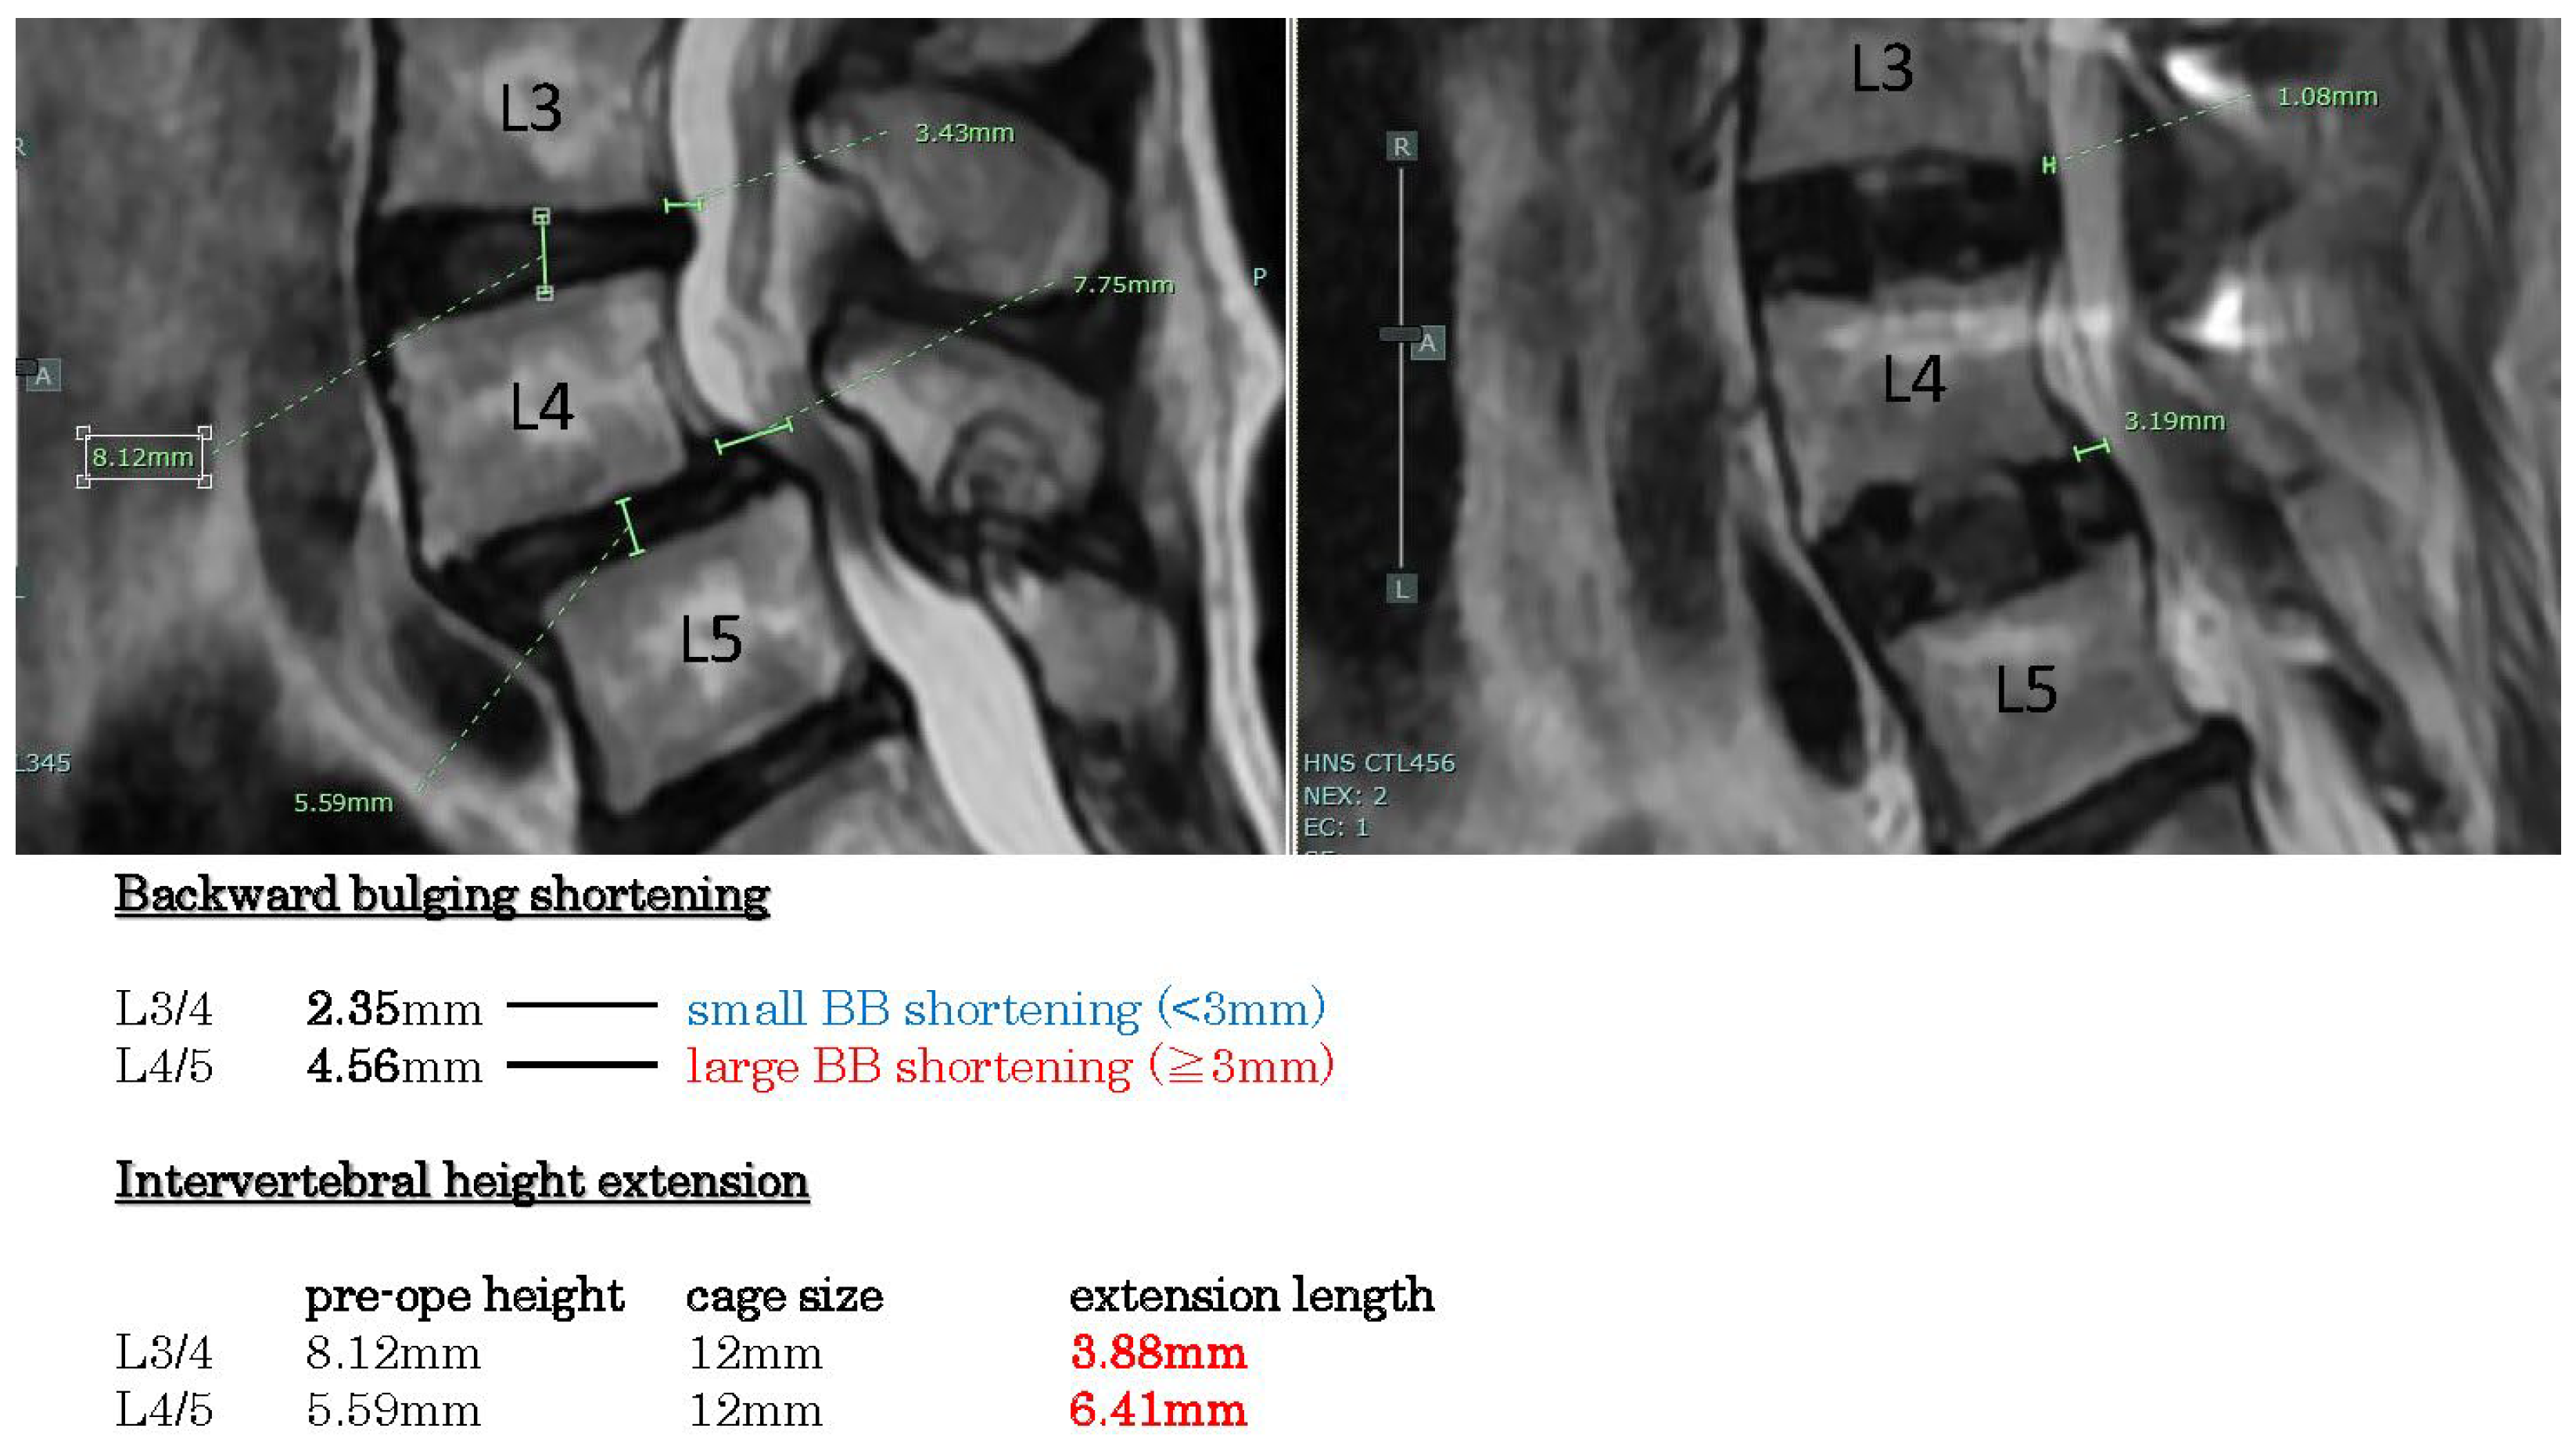

Example case 2 (Figure 4) reveals spondylolisthesis L4/5 with disc hernia L3/4. The backward bulging shortenings are large in L4/5 (>3 mm), but small in L3/4 (<3 mm). Intervertebral height extension lengths are more than 3 mm.

Figure 4. Example case 3, spondylolisthesis with disc hernia. Backward bulging shortenings are large in L 4/5, but small in L3/4. Intervertebral height extension lengths are more than 3 mm.